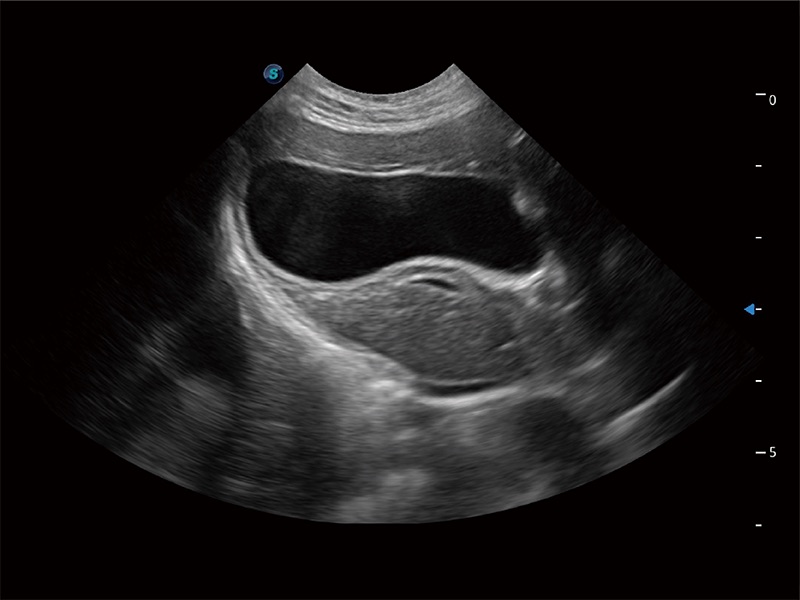

高性能和先进的临床应用工具可以为动物医生提供临床信心。ProPet 80 搭载了先进的腹部和浅表应用工具,帮助医生在日常临床实践中发挥前所未有的作用。

极大提升超低速微细血流的检出能力,同时更精准地滤除软组织和超声信号,为兽用医生提供以往无法通过常规血流获得的疾病诊断信息。